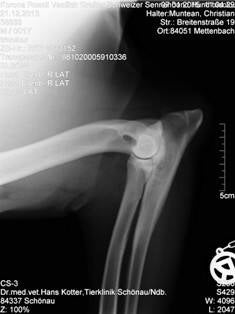

ED - Ellbogendysplasie

ED ist eine chronisch verlaufender Krankheitsverlauf des Ellbogengelenks

schnellwüchsiger Hunderassen.

Grad 0    Normal

Grad 1    Milde Arthrose

Grad 2    Moderate Arthrose

Grad 3    Schwere Arthrose